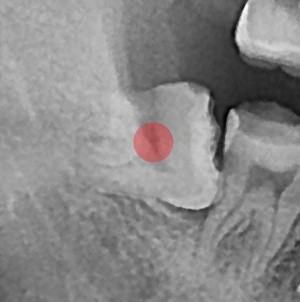

사랑니발치 부분 매복 사랑니 발치